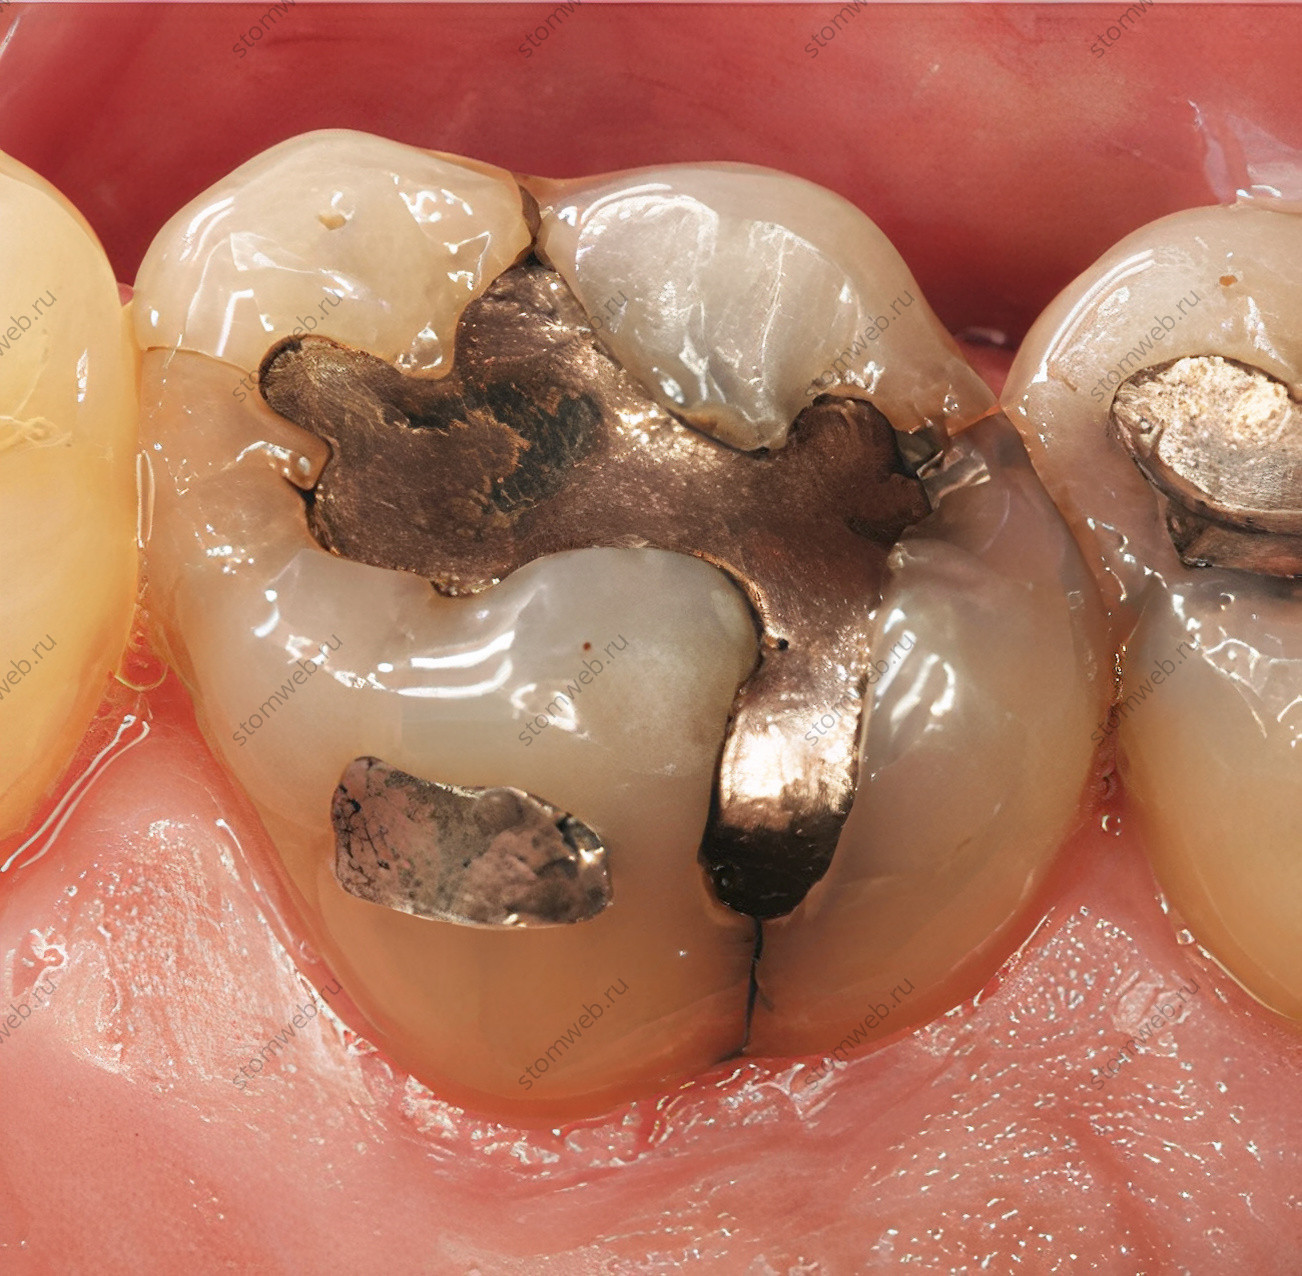

Существуют два первичных фактора, приводящих к образованию трещин: естественные предрасполагающие причины, такие как окклюзионная анатомия и бруксизм, и ятрогенные причины, такие как инструментация и препарирование кариозных полостей. Тот факт, что в зубах с реставрациями часто возникают трещины коронок, побудил многих исследователей оценить ряд реставрационных факторов для определения этиологии нарушений зубов. В некоторых аспектах реставрационная стоматология была отмечена как потенциальный виновник. Самые часто упоминаемые - большие и плохо смоделированные реставрации. Seo и соавт. показали, что использование неадгезивных inlay вкладок из золота или амальгамы повышают риск возникновения продольных трещин в зубах.

Одна из трудностей при постановке диагноза трещины коронки заключается в том, что трещины могут быть скрыты под реставрациями; (рис. 12), кроме того, сломанные зубы не всегда могут быть симптоматичными или могут периодически давать симптоматику. Клинически симптоматичные переломы зубов сбивают с толку, потому что они часто имитируют симптомы других заболеваний, таких как боль в ухе, синусит, дисфункция височно-нижнечелюстного сустава и даже невралгия тройничного нерва и другие неврологические болевые состояния. Когда проблему сложно установить, это может привести к длительному болевому синдрому, который становится более диффузным, делая локализацию пораженного зуба еще более сложной. Многие зарегистрированные случаи длительной орофациальной боли были связаны с обнаружением трещин и переломов в зубах.

Рисунок 12. Моляр верхней челюсти с подозрением на перелом коронки. Мезио-окклюзионную пломбу из амальгамы пришлось удалить, чтобы увидеть трещину (стрелка), которая была прокрашена красным красителем.

Поскольку существующие реставрации могут прятать под собой трещины, необходимо убрать ее для обнаружения линий переломов (рис. 12). Это становится важным этапом обследования, когда симптомы обширны, а боль локализовать невозможно. Brynjulfsen и соавт. методично убирали реставрации по одной с каждого зуба, чтобы обнаружить трещины зубов у пациентов с длительными недиагностированными орофациальными болями.